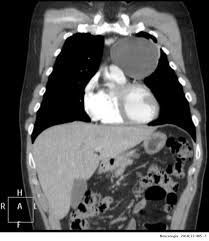

Thymic cyst

A thymic cyst is a benign mediastinal disease which has been reported to be the second most common type of primary mediastinal cyst. Thymic cysts are rare, and the majority are believed to be congenital in origin.